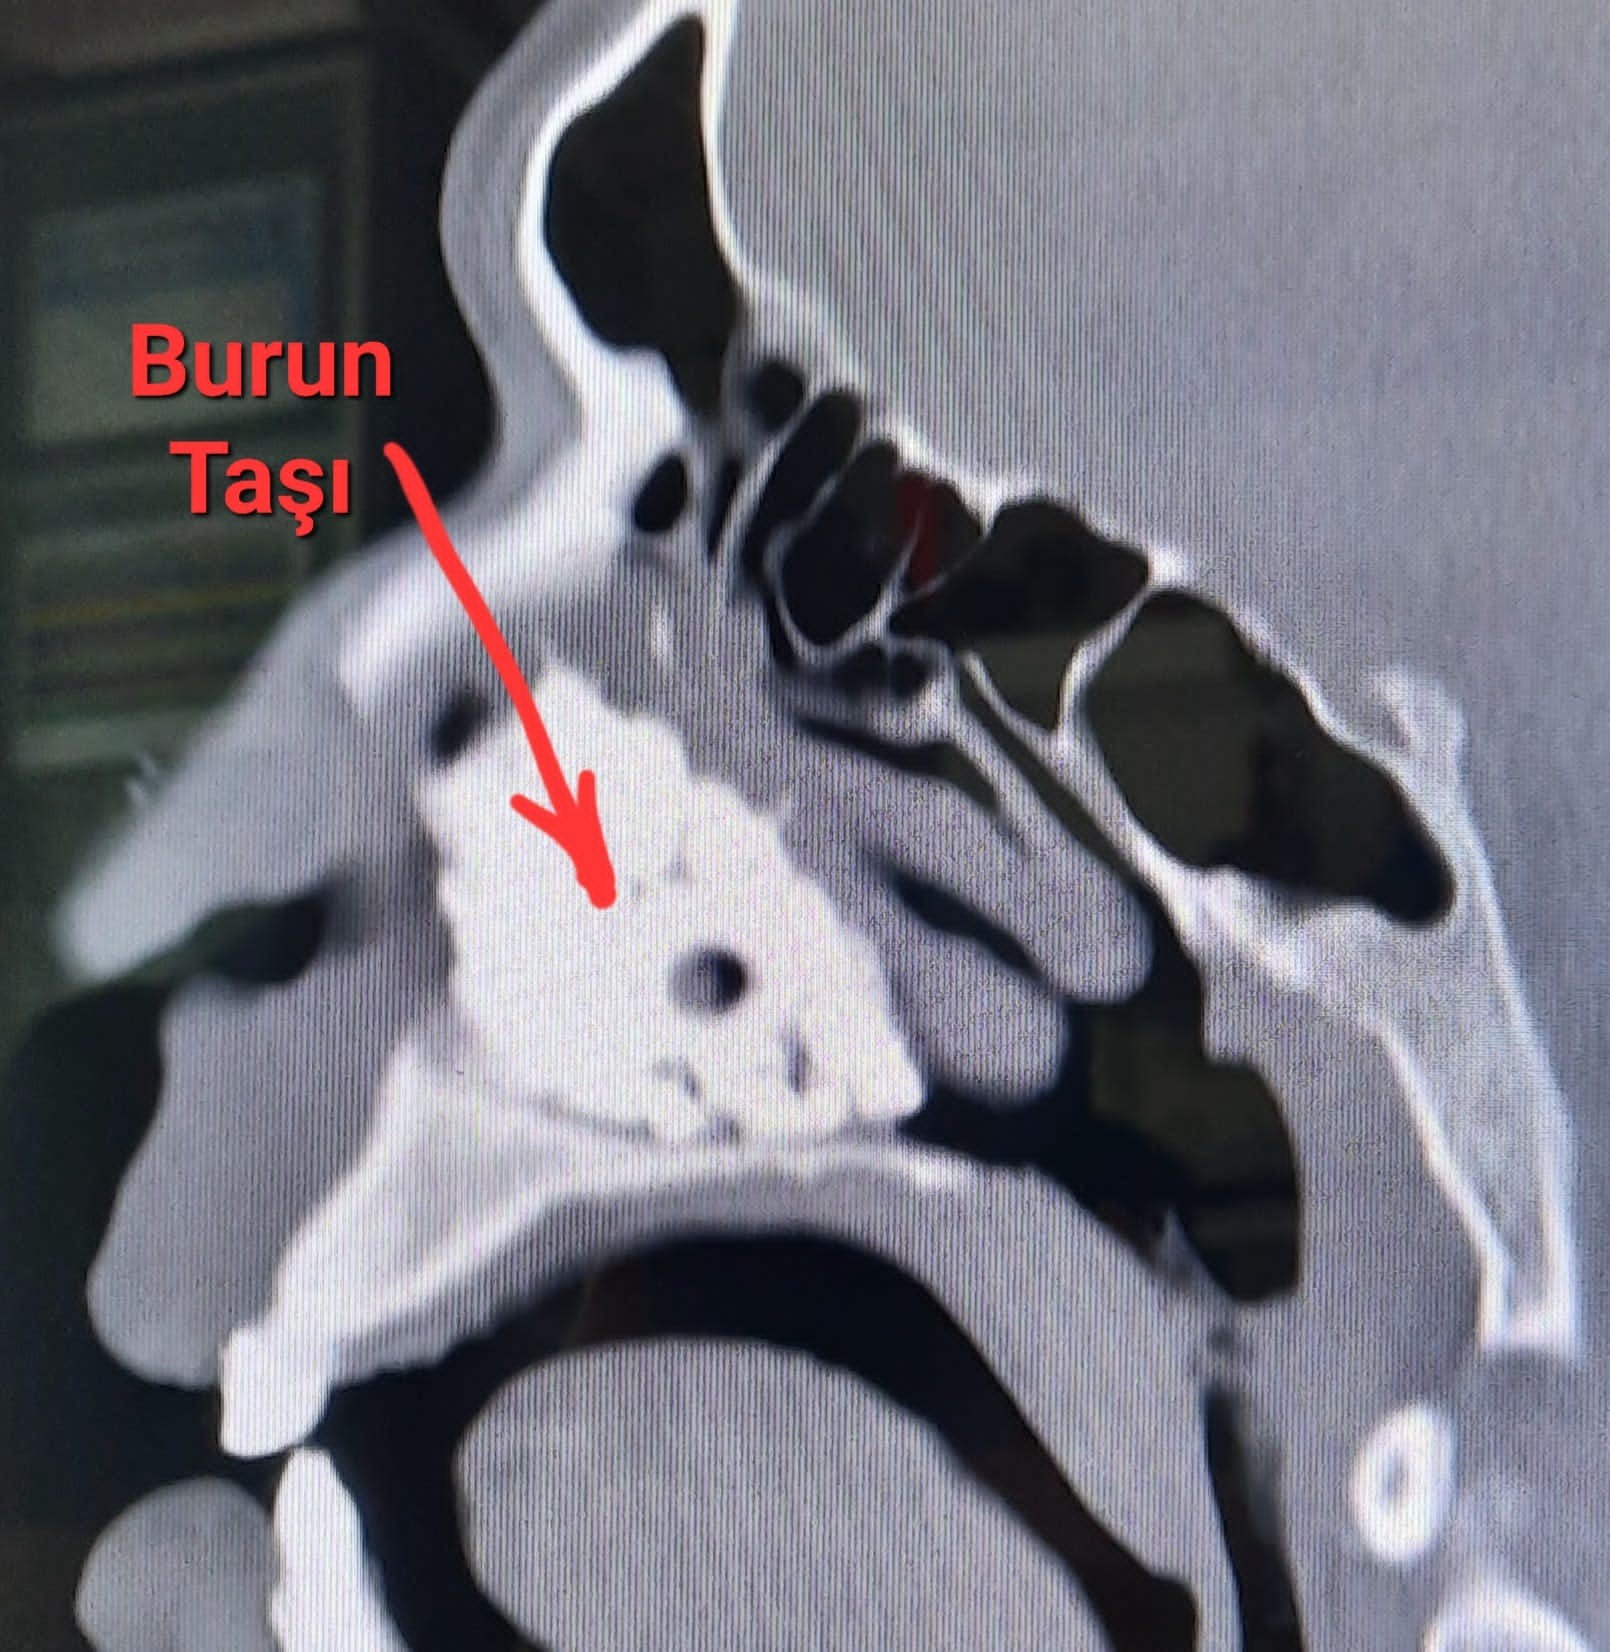

Hastanın tüm şikayetlerinden kurtulduğunu ifade eden Op. Dr. Tuna Kenar, “Hastamız Fatih Ünalan burun tıkanıklığı ve kötü koku nedeniyle bize başvurdu. Hastamızın muayenesini gerçekleştirdiğimizde sol burun boşluğunu tamamen tıkayan beyaz bir kitle saptadık. Kitleye dokunduğumuzda çok sert bir yapısı olduğunu fark ettik ve çok nadir görülen bir hastalık olan burun taşı (rinolit) olduğunu belirledik. Radyolojik görüntülemeler neticesinde burun taşının, burun boşluğunu tamamen kapattığını fark ettik. Hastamızın ifadesinde ise; burun içini ilk defa gördüğünü ve burun taşını görünce şok olduğunu, burun içine bir madde sokmadığını, böyle bir yabancı cismin yaklaşık 30 yıldır olabileceğini belirtti. Hastamızı ameliyata aldık. Ameliyatta kitlenin sert olmasından dolayı diğer dokulara zarar vermemesini sağlamak için parçalayarak çıkardık ve burun boşluğu açıldı. Hastamız ameliyattan sonra artık nefes almakta zorluk çekmediğini ve kötü kokunun gittiğini dile getirdi. Biz de hastamızın bu derecede rahatlamasından çok mutlu olduk” dedi.

Klinik olarak karşılaşılan en sık belirtisinin tek taraflı burun tıkanıklığı ve kötü kokulu burun akıntısı olduğunu, bazen burun kanaması, baş ağrısı, ağız kokusu, burun ve yüzde şişlik de eşlik ettiğini belirten Dr. Kenar; kamera ile (endoskopik) burun içi muayenesi ve burun tomografisi ile tanı konduğunu; tedavide ise burun taşının büyüklüğü, yerleşimi ve etraf dokuya yapışıklık durumuna göre poliklinik veya ameliyathane şartlarında kapalı (endoskopik) burun ameliyatı ile burun taşının çıkarılarak yapıldığının altını çizdi.